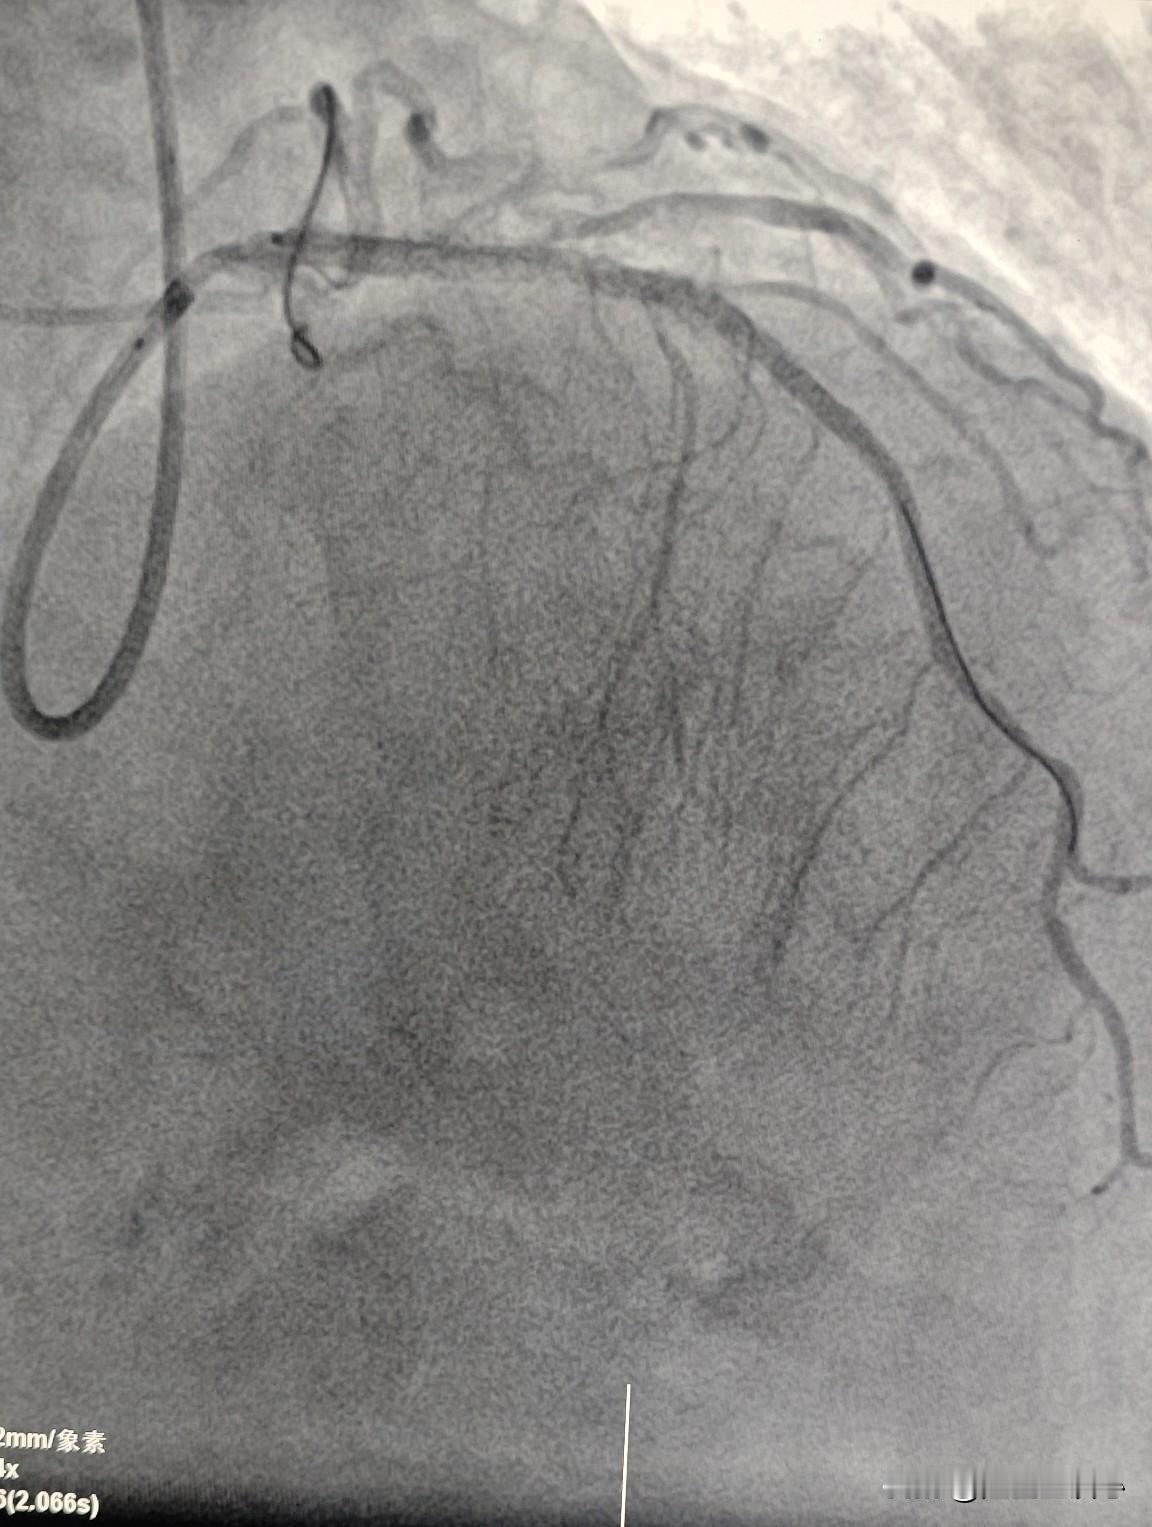

做了心脏支架还抽烟,后果有多严重?18岁男性患者,5 年前做了心脏支架,前降支做了两个。本来有十几年的烟龄,做了支架,不能抽了。4年前,觉得一切都挺好的,也没什么不舒服,就放松了警惕。看到旁边的人抽烟,也跟着吸几口。慢慢的烟瘾又犯了,开始每天两包。 最近半年觉得平常能走1万多步的,现在走5000多步就觉得有胸闷,呼吸困难,觉得不对劲。到医院来复查造影发现前降支的血管里面又出现了新的动脉硬化,其他部位的动脉硬化也加重了。 没办法,又做了一个支架和一个药物球囊。 长期大量地吸烟,损害我们血管的内皮细胞,让胆固醇更容易侵入到血管壁内,形成动脉硬化的斑块。我的动脉硬化的斑块也会再次开始生长。有的病人在原有支架部位又会长出新的动脉硬化斑块,也有的病人在其他的血管长出了新的动脉硬化的斑块。做了心脏支架的朋友们,戒烟刻不容缓。